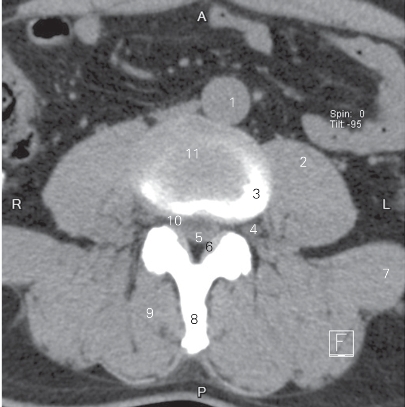

图3-2 经第3/4腰椎间盘的横断层CT图像(软组织窗)

1 腹主动脉 abdominal aorta 2 腰大肌 psoas major

3 第3腰椎椎体 3rd lumbar vertebral body

4 第3腰神经 3rd lumbar nerve

5 蛛网膜下隙 subarachnoid space 6 黄韧带 ligamenta flava

7 腰方肌 quadratus lumborum 8 棘突 spinous process

9 竖脊肌 erector spinae

10 腰椎间孔 intervertebral foramen

11 第3腰椎间盘 3rd lumbar intervertebral disc